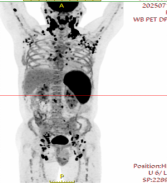

Unfortunately, less than four months after his last chemotherapy session, in June 2025, a mass reappeared in Mr. Wu's neck. It continued to grow and was accompanied by ow-grade fevers. He immediately returned to SRRSH and sought out Dr. Jiang Hao. A repeat biopsy of the neck mass was performed, and the pathology result again confirmed "diffuse large B-cell lymphoma." Genetic testing further revealed a 51% deletion rate of p53 gene. Further investigations showed that lymphoma cells accounted for a staggering 20% of his blood cells. A PET/CT scan also indicated that the number and extent of lymphoma lesions were more severe than during the initial diagnosis (Figure 2). This meant Mr. Wu's lymphoma was an early relapse, significantly more dangerous than his first illness episode. The aggressive nature of the recurrence, resistant to conventional chemotherapy drugs for long-term control, plunged him and his family into deep despair again.

Figure 2